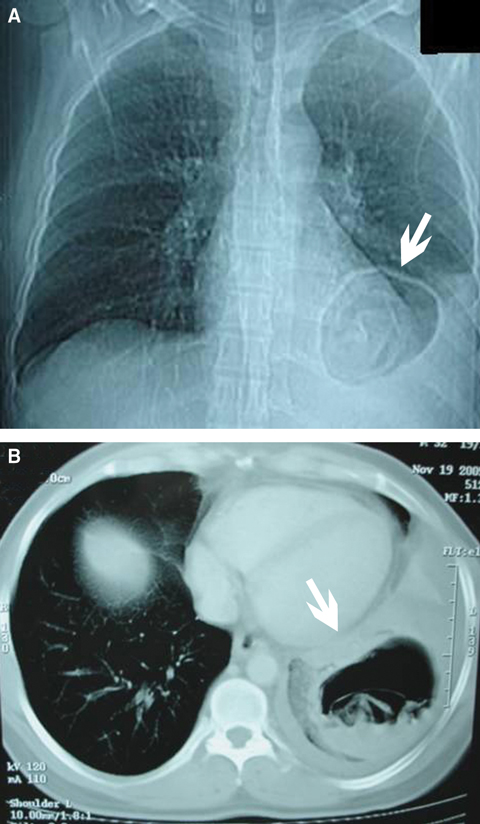

A 32-year-old farmer from rural north-west India presented with a history of paroxysms of cough with expectoration. He owned livestock (hens, goats, cattle and dogs) and lived alongside them. Physical examination was unremarkable except for reduced air entry in the left infra-axillary and infrascapular area. A chest x-ray (Box, A) showed a large, thin-walled cavity containing membranes in the lower lobe of the left lung, together with a left pleural effusion. A contrast-enhanced computed tomography scan of the chest (Box, B) revealed a cyst in the left lower lobe of the lung containing a freely floating endocyst (the “waterlily sign”). The diagnosis of Echinococcus infection (hydatid cyst) was confirmed by positive serology.

The waterlily sign, although rarely seen, is pathognomonic for Echinococcus.